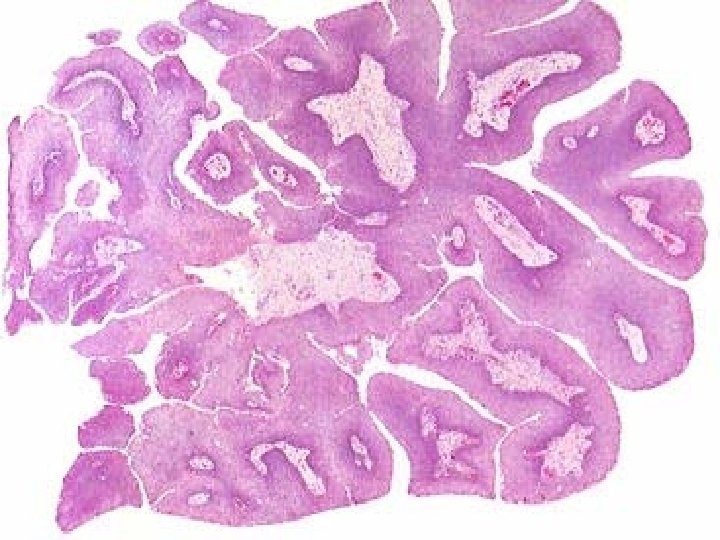

• Laryngeal Papilloma: Site: true vocal cord. Etiology: Human Papilloma virus 6, 11. Gross: small raspberry (rare more than 1 cm). Mic: Finger like projections with fibrovascular core & cover by stratified squamous epithelium.